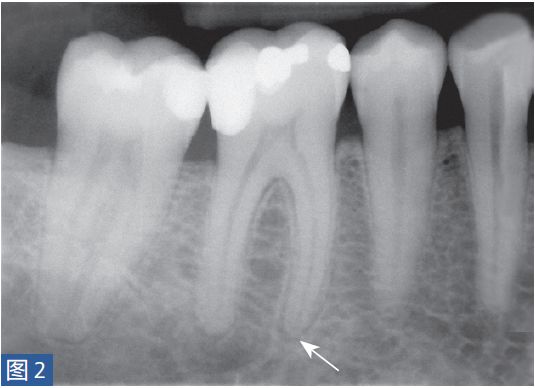

症状性根尖周炎(SAP symptomatic apical periodontitis)从牙髓炎过渡到根尖周炎(图2和3)的发生速度非常快,牙齿表现可能从正常到对冷、热和电刺激的反应越来越强。当牙髓已经完全坏死时,通常会显示对牙髓电活力测试无反应。牙齿可能会有伸长感,用手指或口镜柄施加压力或者振动牙齿会触发非常严重的疼痛。放射学检查可能存在透射区及根周膜间隙增宽,通常硬骨板和牙周韧带没有病理学特征。

图2:46 牙齿SAP。术前X 线片,该牙齿在其他医生处已行龋齿治疗。患者诉牙齿有明显的咬合痛以及强烈的冷热刺激敏感症状。放射学检查,近中根根周膜间隙略增宽。